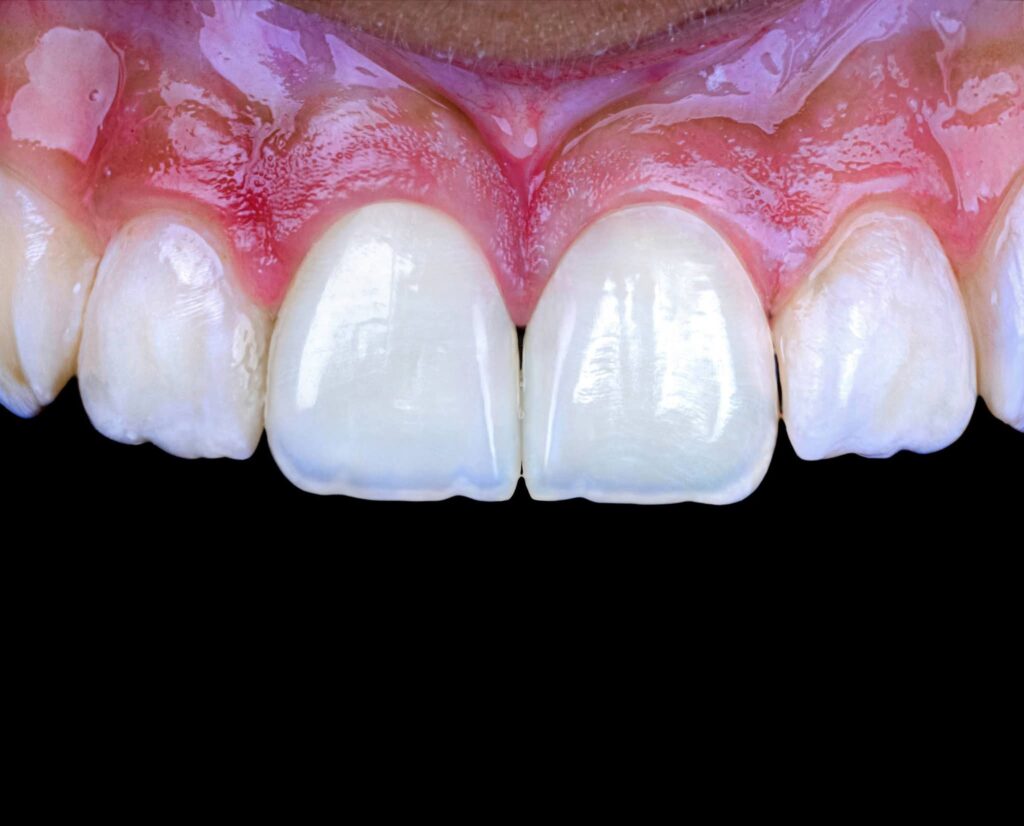

Symmetry and proportionality are fundamental principles in aesthetic dentistry, particularly in direct composite veneers, where the clinician acts simultaneously as a scientist and an artist. Successful veneers are not determined only by color and shape, but by the harmony between teeth, gingiva, lips, and face.

Symmetry refers to the mirror relationship between the right and left sides, especially the maxillary central incisors. Absolute symmetry is not always natural; therefore, perceived symmetry is more important than mathematical symmetry. Small differences in line angles, embrasures, and incisal edges can be used intentionally to create a natural appearance.

Proportionality relates to the width-to-length ratio and the relationship between anterior teeth. The ideal width/length ratio for central incisors is approximately 75–80%, and the apparent width proportion between anterior teeth often follows the golden proportion (~62%), although modern aesthetic dentistry prefers the concept of Recurring Esthetic Dental (RED) proportion for more natural results.

Direct composite veneers require a balance between mathematical proportions and artistic perception. The most aesthetic result is achieved not by perfect symmetry, but by natural, harmonious asymmetry combined with correct proportions.